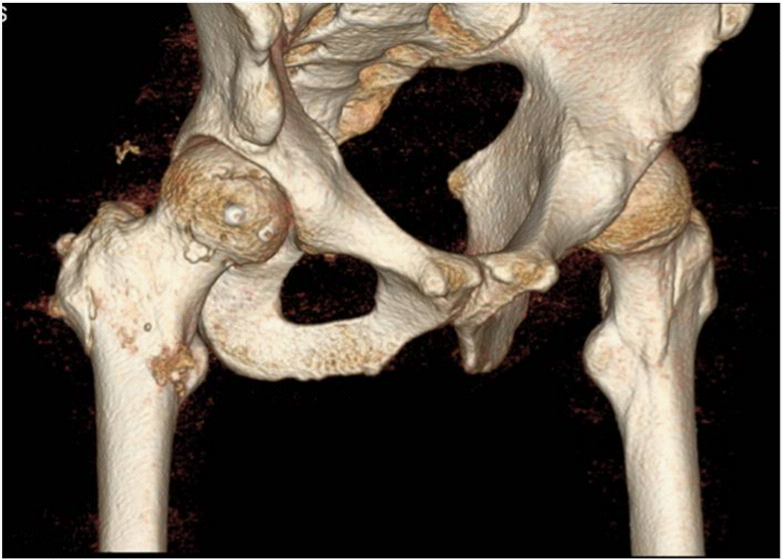

A 27-year-old man was injured by automobile accident and immediately presented to our emergency department. On physical examination, right hip was in flexion, external rotation and abduction. He complained of severe pain, and passive and active movements were not possible in right hip. There was neither neurovascular deficiency nor associated injuries. Radiograph of both hip revealed obturator dislocation of right femoral head and fractured femoral head fragment within hip joint (Figure 1). The dislocation was immediately reduced by traction in line of deformity followed by gentle adduction and internal rotation with pelvis stabilized by an assistant. After closed reduction, anteroposterior radiograph showed femoral head was reduced but crescentic radio-opacity was visible overlying femoral head and translateral radiograph revealed that the fractured femoral head fragment was turned inside out during closed reduction (Figure 2A & 2B). Computed tomogram depicted the 3-D configuration of fracture (Figure 2C & 2D).

We decided to perform open reduction and internal fixation immediately. To preserve posterior vascularity of femoral head, we approached hip joint anteriorly after careful flip osteotomy of greater trochanter. As retracting osteotomized greater trochanter, we were able to find fractured femoral head and its large fragment (Figure 3A). Fractured fragment was measured about 45mm in diameter and was a large part of anteromedial femoral head involving half of ligamentum teres (Figure 3B & 3C). It was possible to perform accurate reduction and rigid fixation of fractured fragment with two Acutrak screws (40mm and 35mm, Acumed®, USA) and careful reduction of dislocated hip was performed (Figure 4A & 4B). Finally we reattached and fixed the osteotomized greater trochanter with three screws. Postoperative simple radiogram and computerized tomogram showed well fixed fracture fragment with mild residual indentation on anterosuperior femoral head (Figure 5A–5C). On postoperative one day, he could ambulate with wheelchair. One week later, he was permitted to walk with crutch while bearing partial weight on his foot. On postoperative one year follow-up, radiogram showed bony union of fractured femoral head as well as osteotomized greater trochanter and healing of fractured posteroinferior acetabular rim without any evidence of secondary osteonecrosis (Figure 6A–6C).

Anterior dislocation of hip is less common than posterior one, comprising only 9-12% of all hip dislocations and has been further classified as pubic(superior), obturator(inferior) and perineal type.2 Anterior dislocation of hip occurs by abduction and external rotation of the hip. Pubic type is caused by extension, whereas obturator type is caused by flexion as additional momentum. At that second, femoral head rests against sharp anterolateral margin of obturator foramen, causing indentation or impaction fracture on the anterosuperior aspects of femoral head. This fractures were usually reported to be located on the posterosuperior and lateral portions of the femoral head.3,4 But, our case was complete fracture of anterior femoral head and the direction of fracture was different from those of previously reported indentation fractures which were from posterolateral to anteromedial. It was on the oblique coronal plane, from anterolateral to posteromedial (Figure 4). Yoon et al.5 reported indentation fracture of femoral head of similar direction, which occurred without hip dislocation and was asserted to be caused by low energy injury in patient with general laxity. But we think the direction of fracture line may be just related to how much the hip is flexed (Figure 7A & 7B).

Vertical shearing could be conjectured as initiating force for fracture based upon indentation and cartilage defect of anterosuperior femoral head (Figure 4A). The possible mechanism of this injury is as follows. At the moment of anterior dislocation in highly flexed position, anterosuperior femoral head became to collide with anterior edge of acetabulum. At this point, medially directed force was abruptly exerted to cause vertical shear fracture of anterosuperior aspect of femoral head (Figure 8A–8C). Van der WerKen et al.6 also proposed that a fracture of the femoral head may precede its dislocation and this fracture is caused by direct blow upon greater trochanter while forces are resisted by firm superior portion of the acetabulum. To cause complete shear fracture, the direction of force should accurately be toward anterior edge of acetabular rim, and the amount and velocity of impact ought to be adequate enough. That is why majority of femoral head fracture reported were just indentation fracture. Rim fracture of posteroinferior acetabulum was caused by abrupt collision of posterosuperior femoral neck with posteroinferior margin of acetabulum on the edge of being dislocated anteriorly. Of OHDs, this case accompanied by complete femoral head fracture is assumed to be caused by high energy injury and advanced form of either indentation fracture of Brumback type 4A or tranchondral shear of Brumback type 4B.7